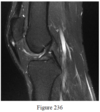

- Figure 236 is the sagittal MR image of a 19-year-old football player. What is the strongest predisposing factor to this condition?

- Playing on soft surfaces

- Hamstring and quadriceps inflexibility

- Lower weight

- Increased quadriceps strength

- Decreased training frequency

- Hamstring and quadriceps inflexibility